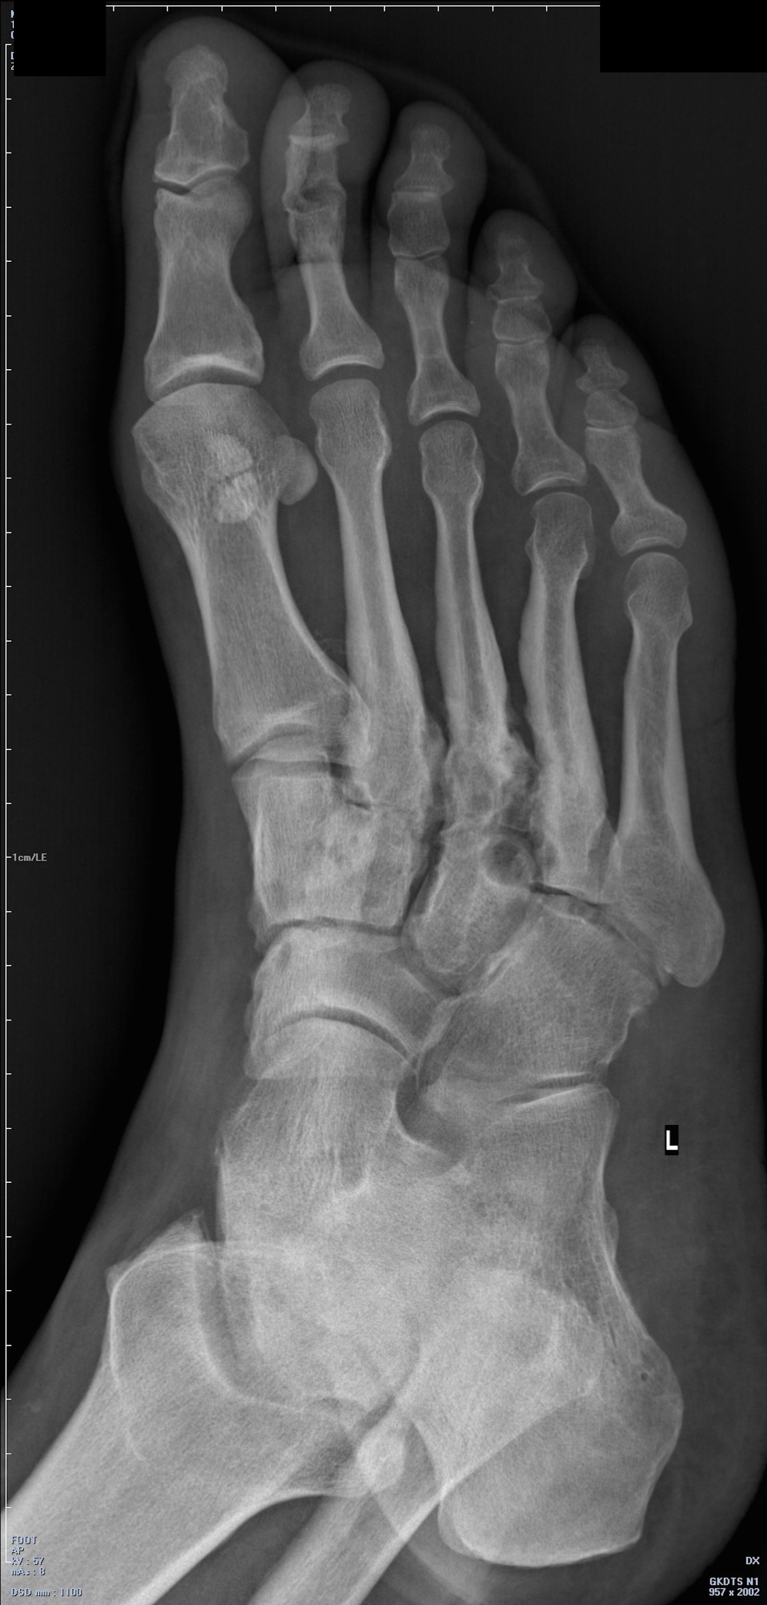

Рентгенограмма стопы: минимально выраженное нарушение структуры 3 плюснеклиновидного сустава (рис. 2). Выполнена МРТ: наличие отека костного мозга не только в рентгенопозитивной зоне, но и в 1 клиновидной и ладьевидной костях (рис. 3).

Рис. 2. Рентгенограмма стопы пациента 1.